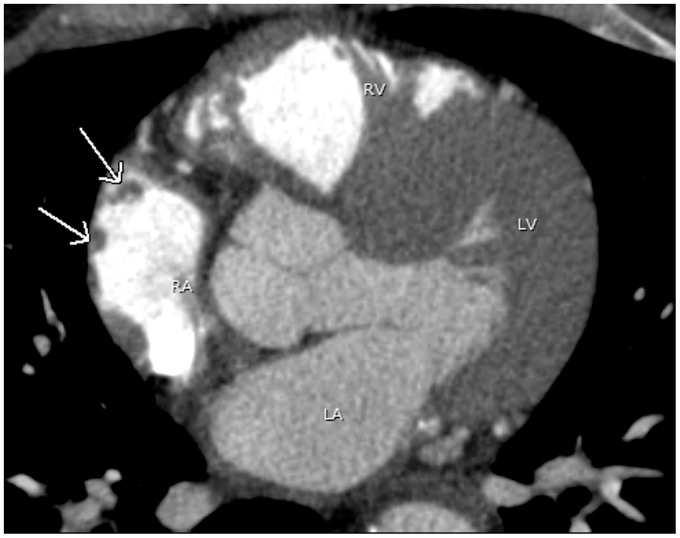

Advances in computed tomography have led to continuous improvement in cardiac imaging. Dedicated postprocessing capabilities, faster scan times, and cardiac gating methods reveal details of normal cardiac anatomy and anatomic variants that can mimic pathologic conditions. This article will review normal cardiac anatomy and variants that can mimic disease. Radiologists should be familiar with normal cardiac anatomy and anatomic variants to avoid misinterpretation of normal findings for pathologic processes.